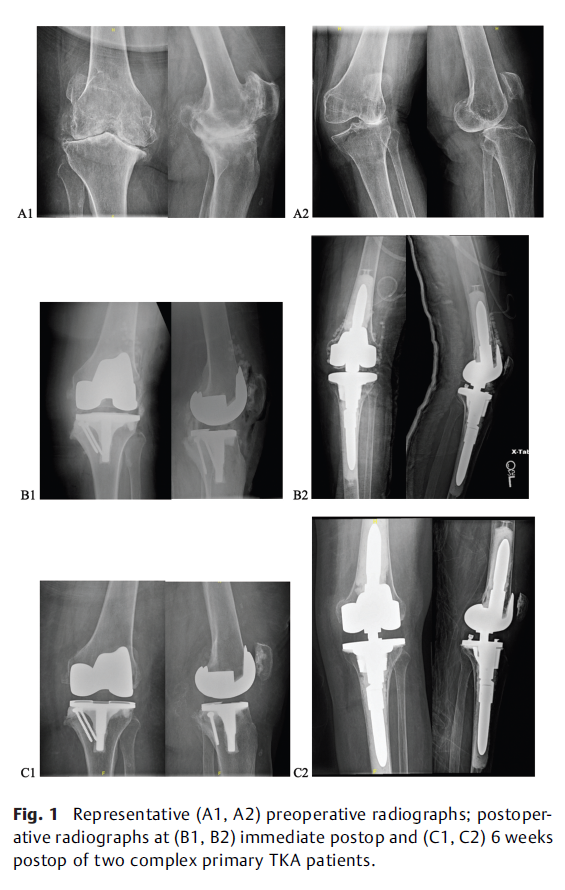

Use of Antibiotic Eluting Calcium Sulfate Beads in High-Risk Primary Total Knee Arthroplasty